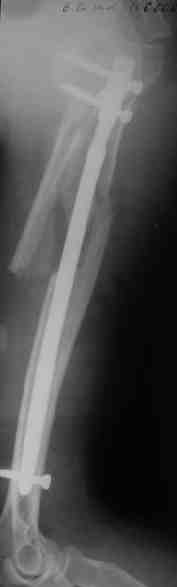

Re: Оскольчатый перелом плеча

Прооперировали больную с переломом плеча все же гвоздем, Фото в приложении.